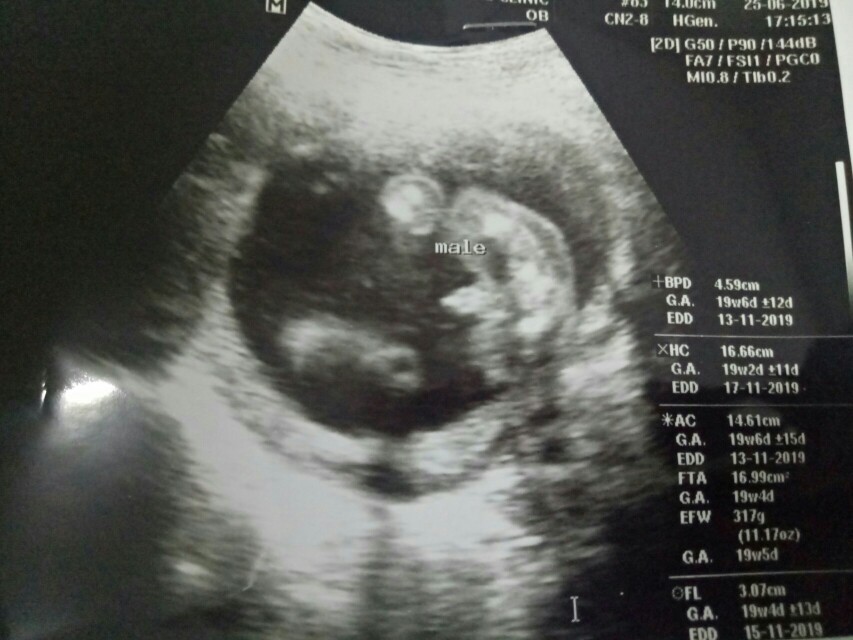

ผู้ชายค่ะ 🥰🥰🥰🥰🥰🥰🥰🥰🥰

บ้านนี้ได้ผู้ชายคะ 👶🏻